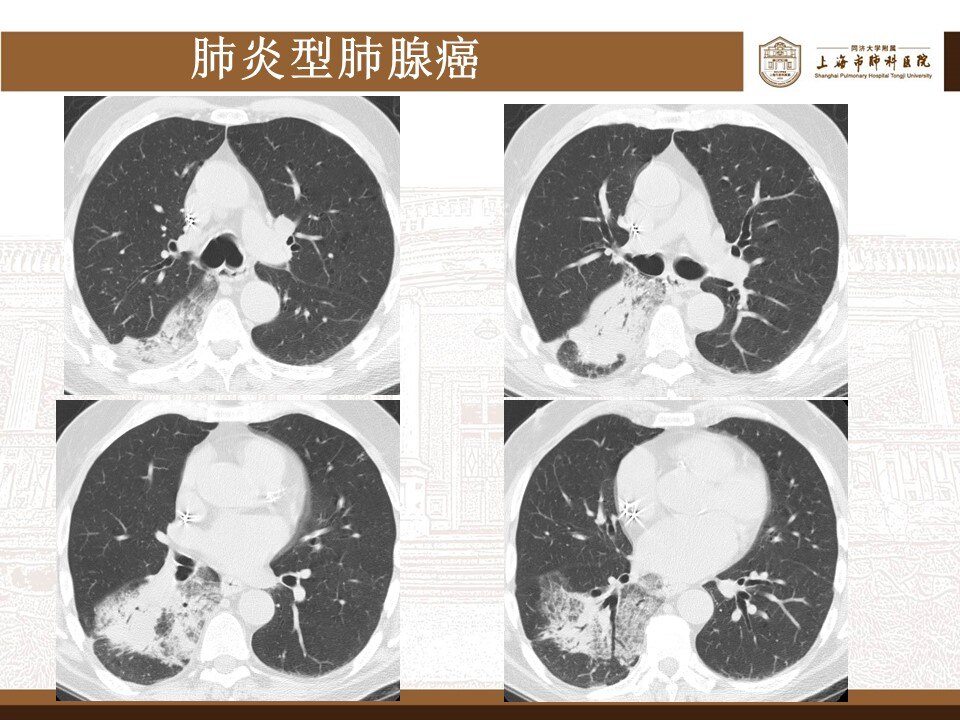

其实,这波omicron感染,确实肺炎比例比想象中要高,但很多都不会是大白肺,多数表现为双肺散发磨玻璃影,当然,也有单独的磨玻璃结节,特别容易表现为混合密度磨玻璃结节。其实很多新发的磨玻璃结节都是新冠肺炎,不用过于紧张,如果感染面积不大,一般临床上,也不需要特异性治疗,休息观察就行了。